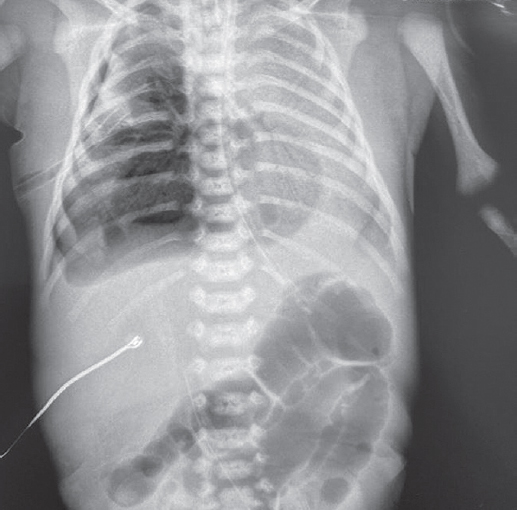

The article presents a case of successful treatment of acute respiratory distress syndrome in a full-term newborn complicated by pulmonary barotrauma using monobronchial administration of exogenous surfactant under X-ray control. In order to assess the course of the disease and the effectiveness of treatment, a retrospective analysis of medical documentation was carried out. From the first minutes of life, the child had respiratory disorders, which was the basis for non-invasive mechanical lung ventilation — nCPAP (nasal continuous positive airway pressure). Progression of hypercapnia and hypoxemia was revealed over time, and therefore tracheal intubation was performed and convective mechanical ventilation was started with FiO2 = 1,0. Monobronchial administration of exogenous surfactant was a key element of the therapy that allowed to achieve stabilization of the condition and regression of gas exchange disorders with complete recovery of the patient.

Monobronchial administration of surfactant in acute respiratory distress syndrome with heterogeneous lung involvement is an effective treatment option and can be used in clinical practice for refractory hypoxemia.